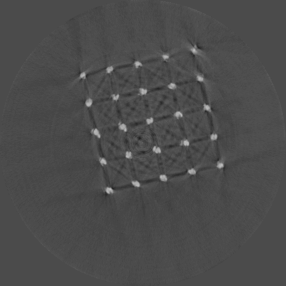

Beam hardening and metal artefacts pose challenges during CT imaging in the presence of metal hardware [17]. This paper presents data that demonstrates the use of spectral imaging in reducing beam hardening effects and metal artefacts. A high-Z sensor layer like CdTe is necessary to provide improved spectral resolution at higher x-ray energies needed for typical implant visualisation. Multi-energy acquisition of metal samples has the added advantage of capturing spectral information which exhibits reduced artefacts and reasonable non-metal (tissue) information. Further, the results were obtained without any hardware filters (except for the intrinsic filter-equivalent in the x-ray tube) and without any numerical corrections. A global reduction in noise due to charge sharing effects was seen due to the availability of CSM. 3D visualisation of the samples (figure 9) revealed finer spatial structures.

Refer to caption

(a) Porous Ti scaffold

(b) Mg scaffold

(c) Ti mesh

Figure 9: High resolution MARS-Exposure Render visualisation of the metal samples